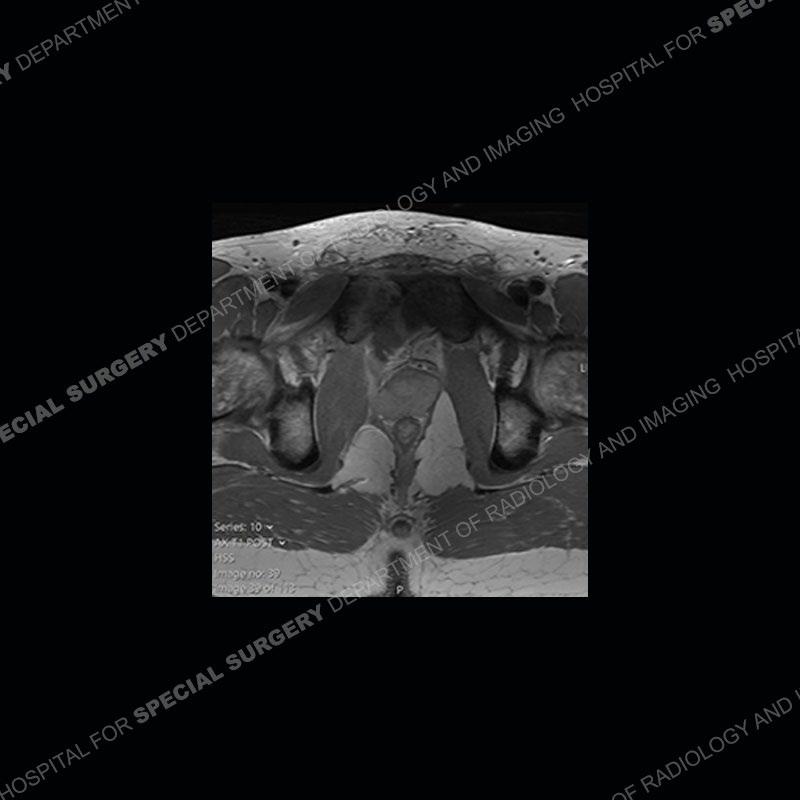

Radiographs did not demonstrate any clear abnormality. The MRI shows markedly abnormal signal of the right superior pubic ramus and abnormal signal/”mass” extending into the adjacent soft tissue. The inferior articular surface of the ramus showed what was thought to be bony destruction. CT examination shows a destructive process of the right superior pubic ramus.

Subsequent MRI in a very short time interval shows markedly increased abnormality of the ramus and increased edema and “mass” of the soft tissue. Post contrast imaging shows multiple, rim enhancing collections of the soft tissue and similar albeit less conspicuous enhancing collection of the ramus.

This case was a bit surprising to all involved given that the young man is otherwise in good health and extremely active in sports. The original thought was this case was going to be an overuse injury or stress fracture. The pubic ramus with the adjacent physis acts as a metaphyseal equivalent and although not frequently thought of would be a reasonable location for infection/osteomyelitis. The first MRI was somewhat confusing as the process did not have an appearance of a stress injury or rectus adductor aponeurosis injury. The degree of edema of the bone and soft tissue together would be odd especially for a sports hernia process. Initially, the thought was of an aggressive process which could be infection or neoplastic. Particularly, the abnormal architecture of the inferior surface of the ramus looked like a destructive process.

The repeat MRI, with the marked degree of increased abnormality of the bone and soft tissue shifted the diagnosis to a high degree towards infection. Even the most aggressive of neoplasms would not have that the degree of change in a 3-day time span. The CT study was shown before the repeat MRI but actually occurred just after the repeat MRI. It helped confirm the destructive process of the ramus and particularly the abnormal architecture along the inferior margin. The patient went on to have a CT guided aspiration of one of the soft tissue collections with 4cc of purulent fluid obtained. A surgical irrigation and debridement of the bone and soft tissue was performed. A PICC line was placed and the patient is currently undergoing IV antibiotic treatment with a possible repeat irrigation and debridement.